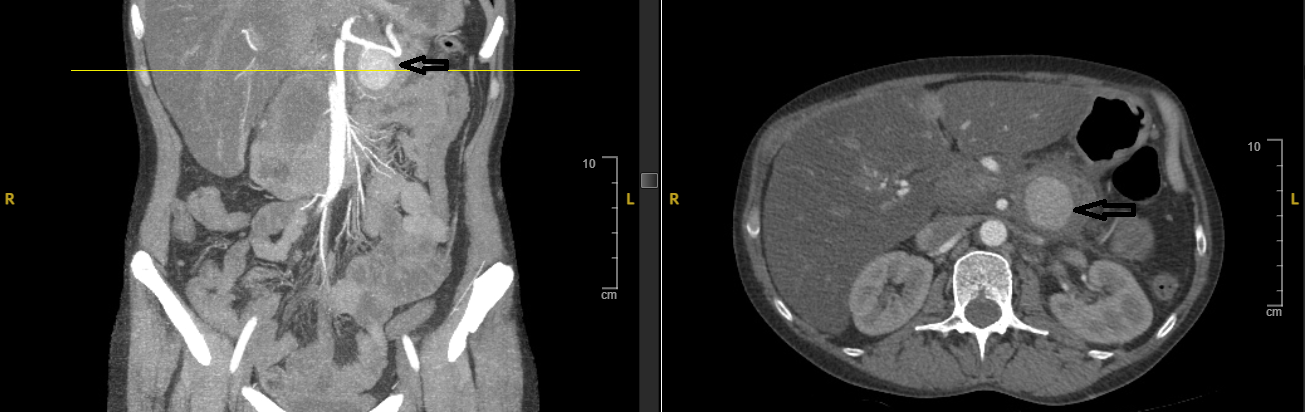

2. Case Presentation